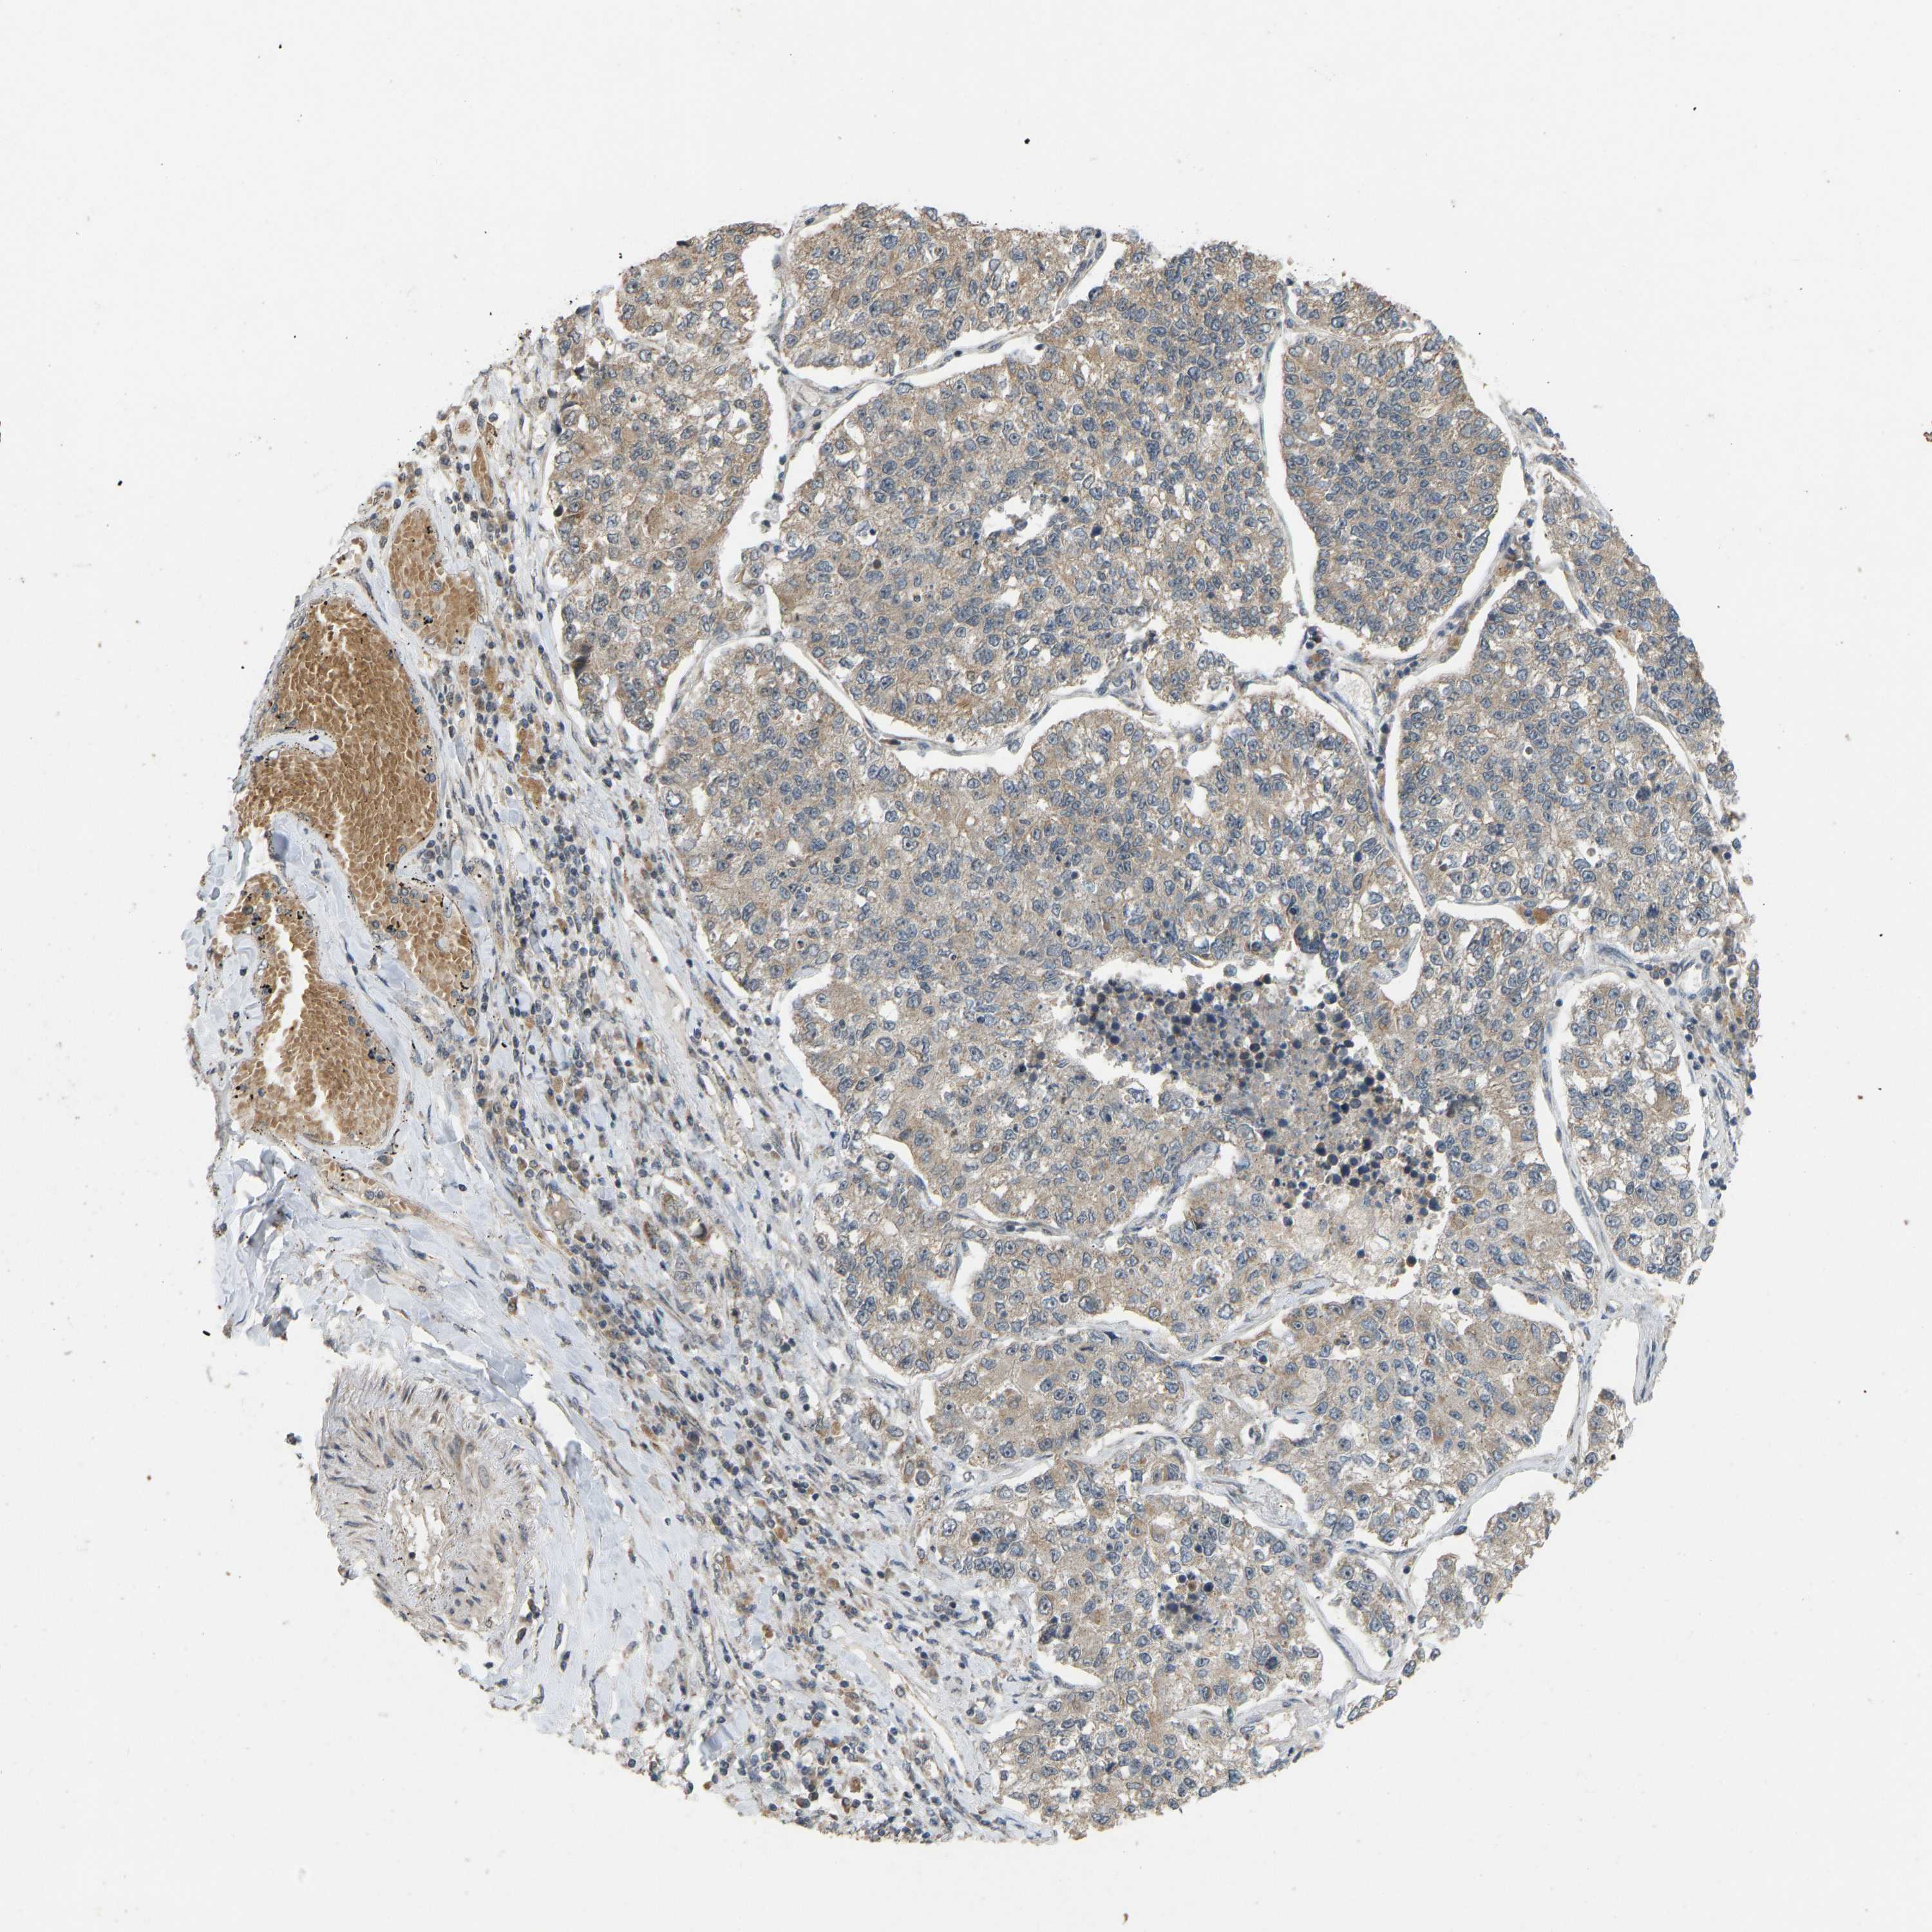

LUNG ADENOCARCINOMA (VALIDATION) - Interactive survival scatter ploti

The Survival Scatter plot shows the clinical status (i.e. dead or alive) for all individuals in the patient cohort, based on the same data that underlies the corresponding Kaplan-Meier plots. Patients that are alive at last time for follow-up are shown in blue and patients who have died during the study are shown in red.

The x-axis shows the expression levels (FPKM) of the investigated gene in the tumor tissue at the time of diagnosis. The y-axis shows the follow-up time after diagnosis (years). Both axes are complimented with kernel density curves demonstrating the data density over the axes. The top density plot shows the expression levels (FPKM) distribution among dead (red) and alive patients (blue). The right density plot shows the data density of the survived years of dead patients with high and low expression levels respectively, stratified using the cutoff indicated by the vertical dashed line through the Survival Scatter plot. This cutoff is automatically defined based on the FPKM cutoff that minimizes the p-score. The cutoff can be changed by dragging the vertical line or by entering a cutoff value in the square labeled "Current cut-off".

Under the Survival Scatter plot the p-score landscape (black curve; left axis) is shown together with dead median separation (red curve; right axis). Dead median separation is the difference in median mRNA expression between patients who have died with high and low expression, respectively. It is calculated as follows: median FPKM expression of dead patients with high expression - median FPKM expression of dead patients with low expression. This is intended to aid the user in visually exploring custom cutoffs and the associated p-scores and dead median separation.

Individual patient data is displayed and can be filtered by clicking on one or more of the category buttons on the top of the page. Categories describing expression level and patient information include: high, low, alive, dead, female, male and tumor stages. The scale of the x-axis can be toggled between linear and log-scale by clicking on the "x log" button. Mouse-over function shows TCGA ID, patient information and mRNA expression (FPKM) for each patient.

& Survival analysisi

Kaplan-Meier plots summarize results from analysis of correlation between mRNA expression level and patient survival. Patients were divided based on level of expression into one of the two groups "low" (under cut off) or "high" (over cut off). X-axis shows time for survival (years) and y-axis shows the probability of survival, where 1.0 corresponds to 100 percent.

ACADS is not prognostic in Lung Adenocarcinoma (validation)

: 3.31

Average pTPM 6.5

Number of samples 105